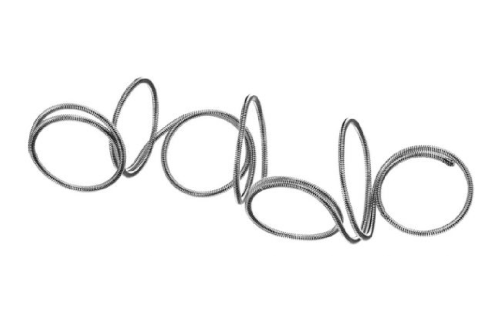

Em Cirurgia Vascular, Endovascular e Radiologia Intervencionista oferecemos uma ampla gama de soluções, incluindo enxertos endovasculares, cateteres de trombectomia e dispositivos de embolização. Esses produtos são vitais para o tratamento de doenças vasculares complexas, como aneurismas e tromboses, proporcionando aos profissionais de saúde as ferramentas necessárias para intervenções precisas e eficazes.

Nossa atuação em Neurorradiologia Intervencionista inclui a oferta de microcateteres e stents especializados para o tratamento de aneurismas cerebrais e outras condições neurológicas críticas. Esses dispositivos são desenvolvidos com tecnologia de ponta para garantir a máxima segurança e eficácia durante os procedimentos, ajudando a preservar a integridade cerebral dos pacientes.